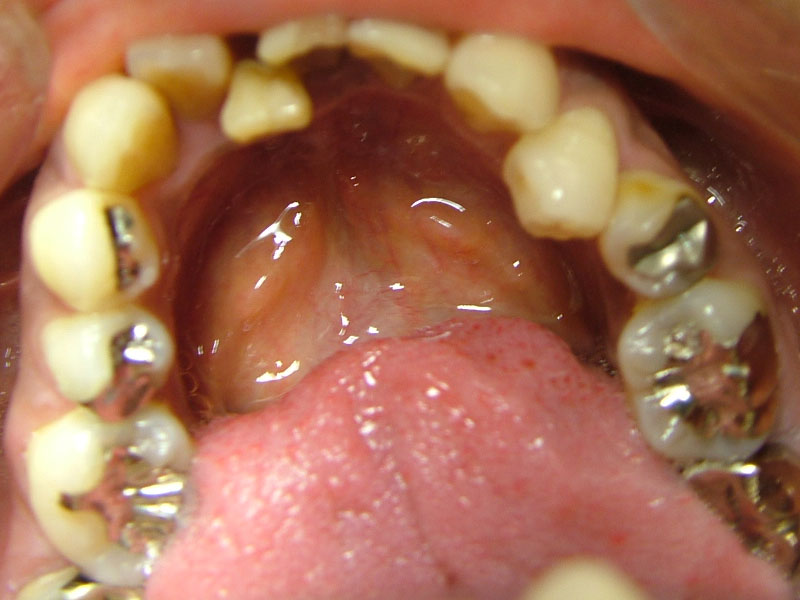

術前

- 初診:2006年。2010年―矯正治療を含めた一口腔単位の治療開始、治療当時、30代女性、喫煙者

- 主訴:虫歯治療、歯周病治療、できれば歯並びも治したい。

- 矯正診断:3級骨格性の反対咬合

- 治療方針:以前に治療した歯の再治療(虫歯治療、歯内療法、歯周処置)、右下前歯1本抜歯、矯正用インプラントを用いたワイヤー矯正、修復処置(被せ物)、保定(上ワイヤー、下マウスピース)、歯茎のピーリング(漂白)、4か月メンテナンス